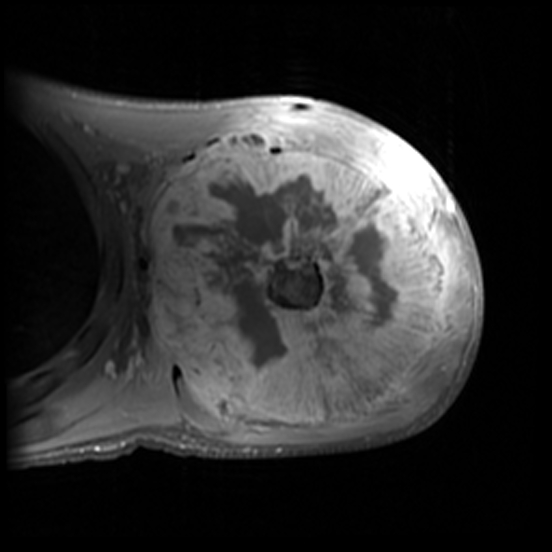

Врач высшей категории, врач-рентгенолог отделения лучевой диагностики клинического госпиталя Лапино группы компаний «Мать и дитя».

врач травматолог-ортопед, рентгенолог, автор методики "Рентген на дому"